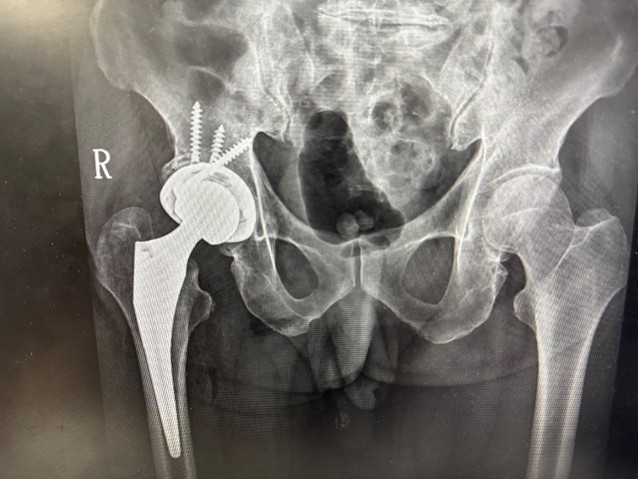

76歲男性多年前因髖臼骨折接受手術,術後留下垂足(foot drop)與步態異常,長期行動不便,導致外傷性退化性髖關節炎,連如廁與行走都成為挑戰。經新竹臺大分院骨科團隊詳細評估並與病人充分溝通後,決定採用「前側入路(Direct Anterior Approach, DAA)」人工髖關節置換手術,避開之前的手術區域,病人術後當天即可床邊如廁並下床行走,疼痛顯著減輕。

新竹臺大分院骨科部主任賈維焯醫師指出:「DAA手術的最大優勢在於保留肌肉結構、縮小傷口並降低疼痛,使病人能於術後儘早下床活動,加速恢復日常生活功能。」

賈維焯主任說明,DAA人工髖關節置換術是近年國際間發展成熟的微創技術。新竹臺大分院骨科團隊結合術前影像分析與精準定位系統,提高手術植入穩定性與下肢長短對位準確性。與傳統後側入路手術相比,DAA術式不僅可減少術後疼痛與出血,亦能縮短復健期並降低脫臼風險。